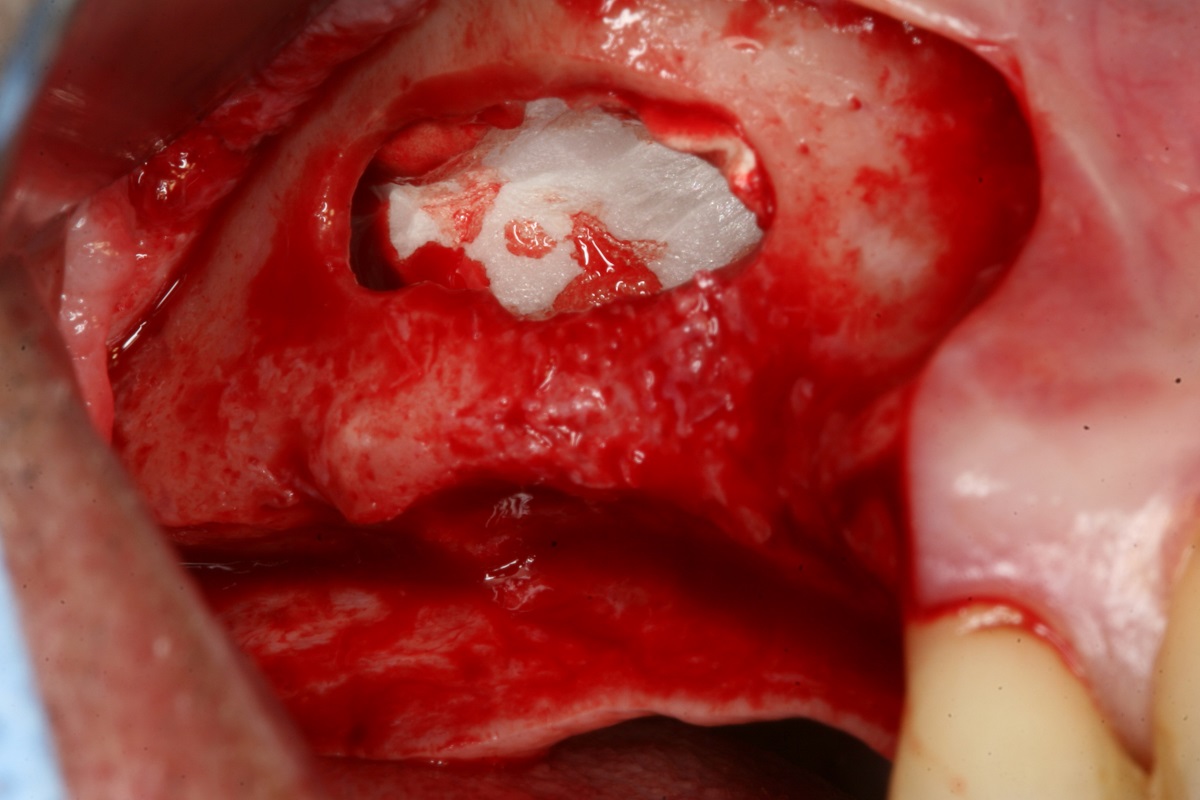

06/14 - Augmentation of the sinus wall with a mixture of autologous bone and maxresorb®

Two-stage sinus lift with maxresorb® & collprotect® - Dr. S. Kistler